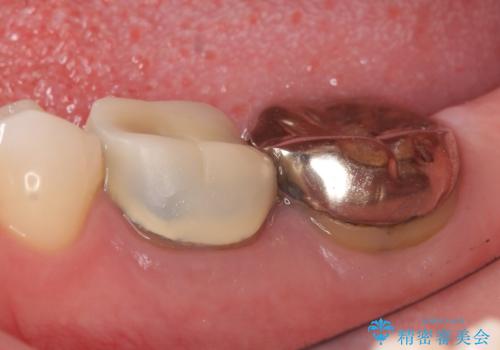

外れそうで不適合のかぶせ物の根管治療からの再治療